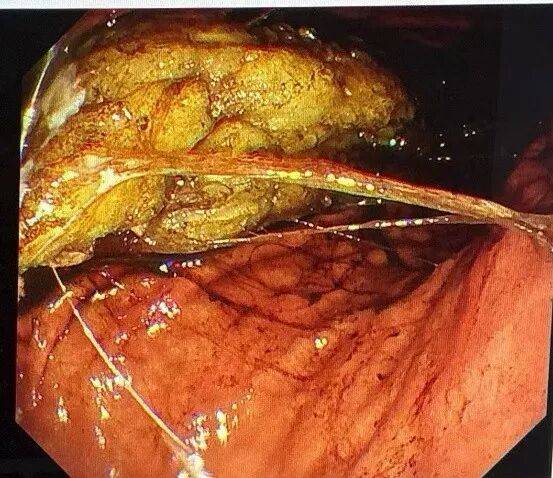

一位68岁中老年女性患者,主因“间断上腹部绞痛3天”前来就诊,患者自述3天前进食较多山楂等食物后间断出现上腹部绞痛、夜间为甚,无恶心呕吐、无腹泻、无发热;无头晕头痛、无胸闷胸痛,纳少,眠一般,二便可。入院后完善相关检查,胃镜提示:胃底、体粘液池可见大量暗红色内容物,腔内可见一枚大小约8*7cm胃石,另见大量食物残渣,影响观察。质稍软,予以异物钳、圈套器勒扎,石体成若干小块。胃角可见一巨大溃疡,予内镜下处理。